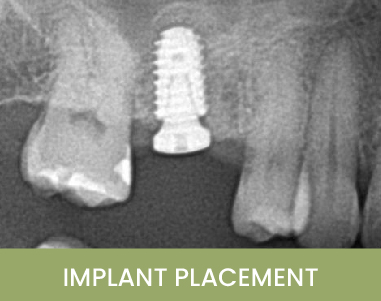

This patient had been missing upper left posterior teeth for an extended period. After careful evaluation and digital treatment planning, two implants were placed using a surgical guide in a minimally invasive manner. The implants were positioned with ideal spacing between each other and the adjacent teeth, providing the best outcome for long-term maintenance. The implants were restored three months later, giving the patient comfort and normal function once again.